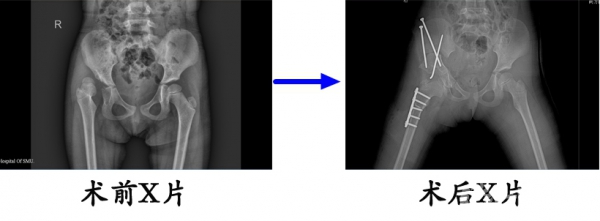

2.改良三联截骨

李某某,右侧发育性髋关节发育不良,在我院行改良三联截骨后,复位良好。